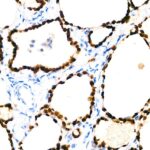

Images of TTF1 Rabbit mAb (A22248)

Immunohistochemistry analysis of paraffin-embedded human thyroid using NKX2-1 Rabbit mAb (A22248) at dilution of 1:100 (40x lens).Perform high pressure antigen retrieval with 10 mM citrate buffer pH 6.0 before commencing with IHC staining protocol.